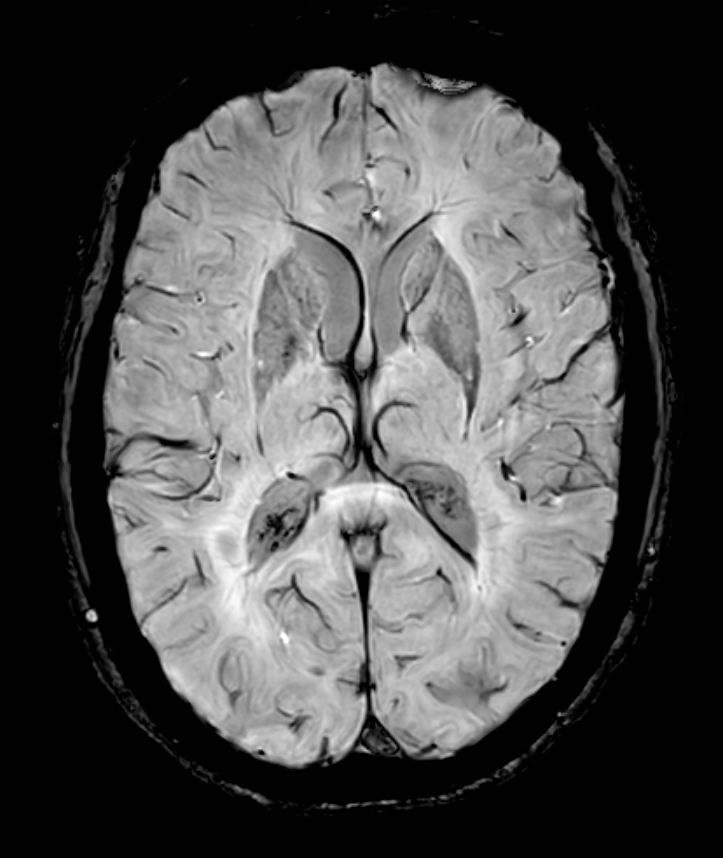

SWIp 6 echoes (Modulus)

SWIp 6 echoes (minIP)

SWIp 6 echoes (Phase)